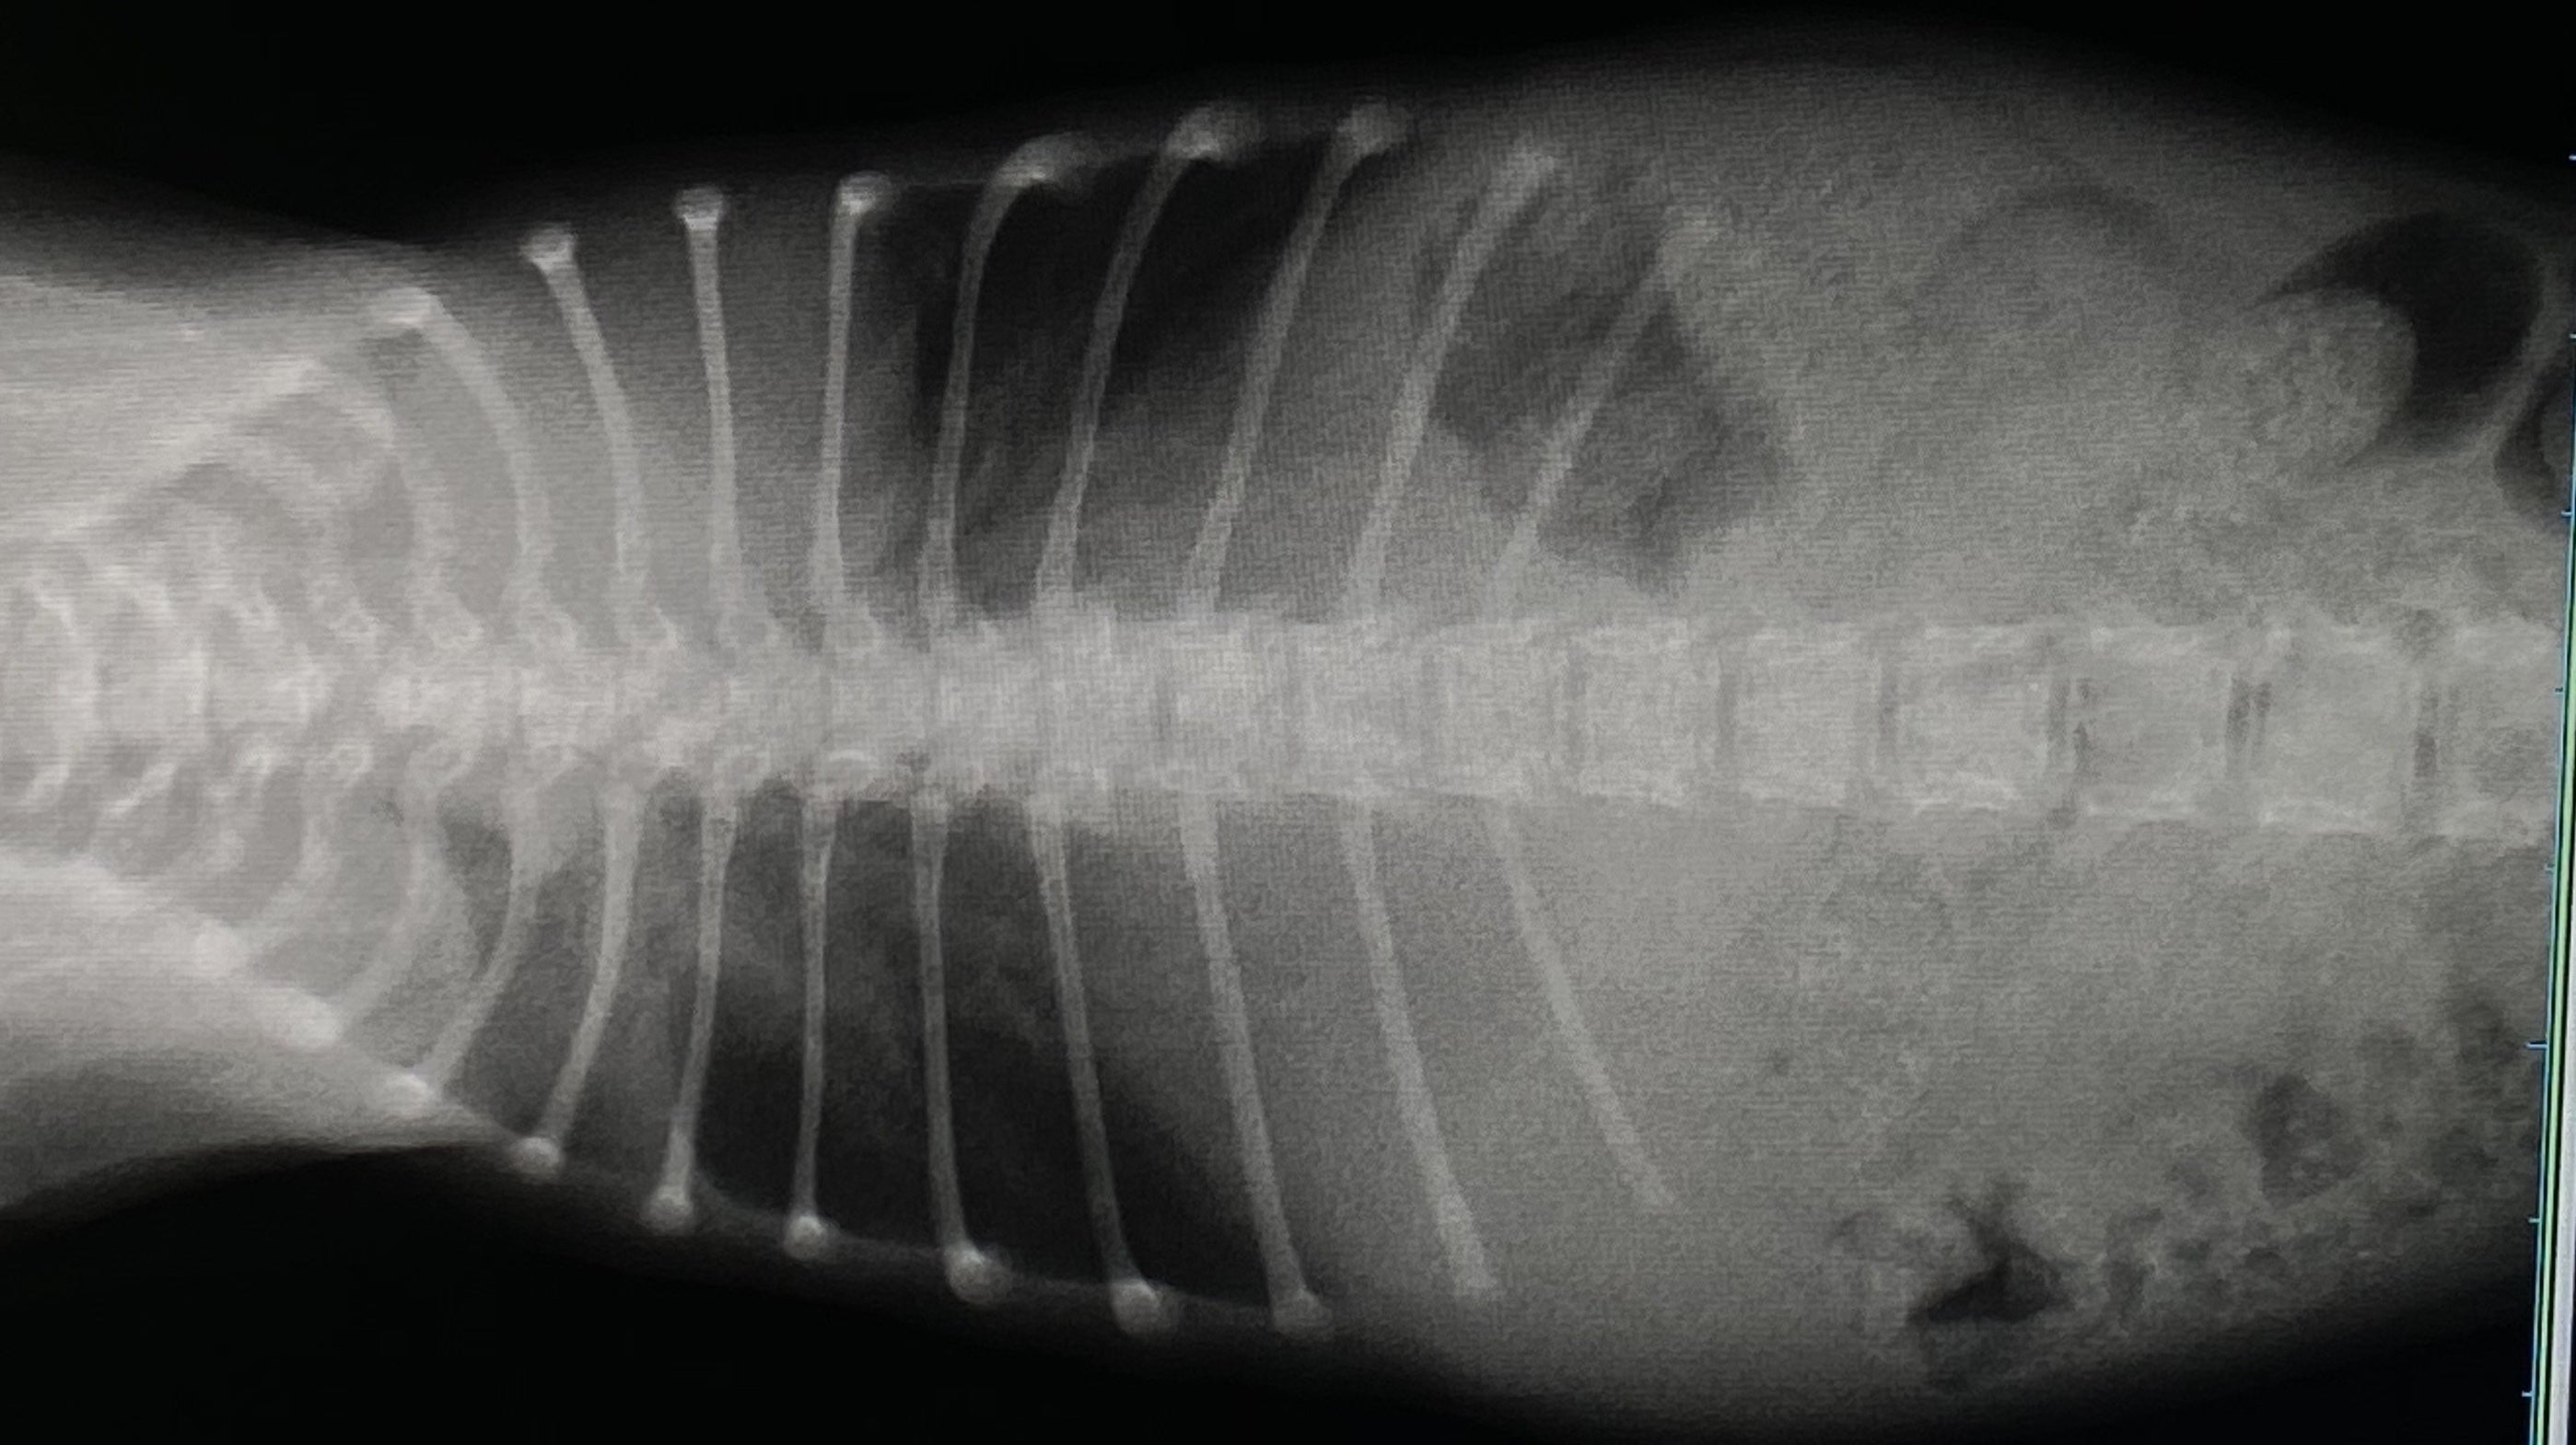

うどんちゃんが1ヶ月半になった先日、胸部の異常に気付き病院にかかりました。病院ではいわゆる奇形で重度の漏斗胸だと診断されました。

レントゲンを見た感じだと肋骨が内蔵(心臓)にくい込んでいる(通常じゃ有り得ないことなのでまだ未確定)可能性があり手術の難度も上がり、費用も通常よりもかなり高額になるとの事です。

肋骨も庇うためか歪んでしまっていました。。

肺も小さいので肺活量がかなり少なく、すぐにバテて動けなくなります…